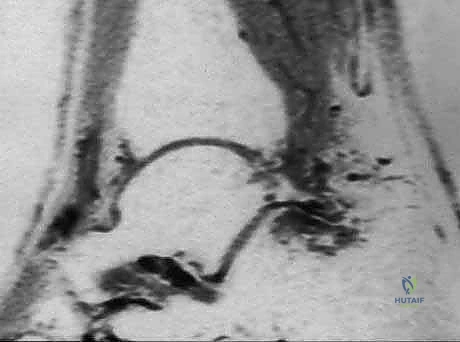

شكل 3: صورة رنين مغناطيسي (MRI) تظهر بوضوح التورم والالتهاب (اللون الأبيض الساطع) في الأنسجة الرخوة والعظم المثلثي في الجزء الخلفي من الكاحل.

| الرنين المغناطيسي (MRI) | تقييم الأنسجة الرخوة والالتهابات | يظهر وذمة نخاع العظم (Bone Marrow Edema) في العظم المثلثي، التهاب السائل المفصلي، التهاب وتر الـ FHL، وتمزق الأربطة. | المعيار الذهبي (Gold Standard) لتأكيد التشخيص وتحديد مدى تضرر الأنسجة المحيطة. |